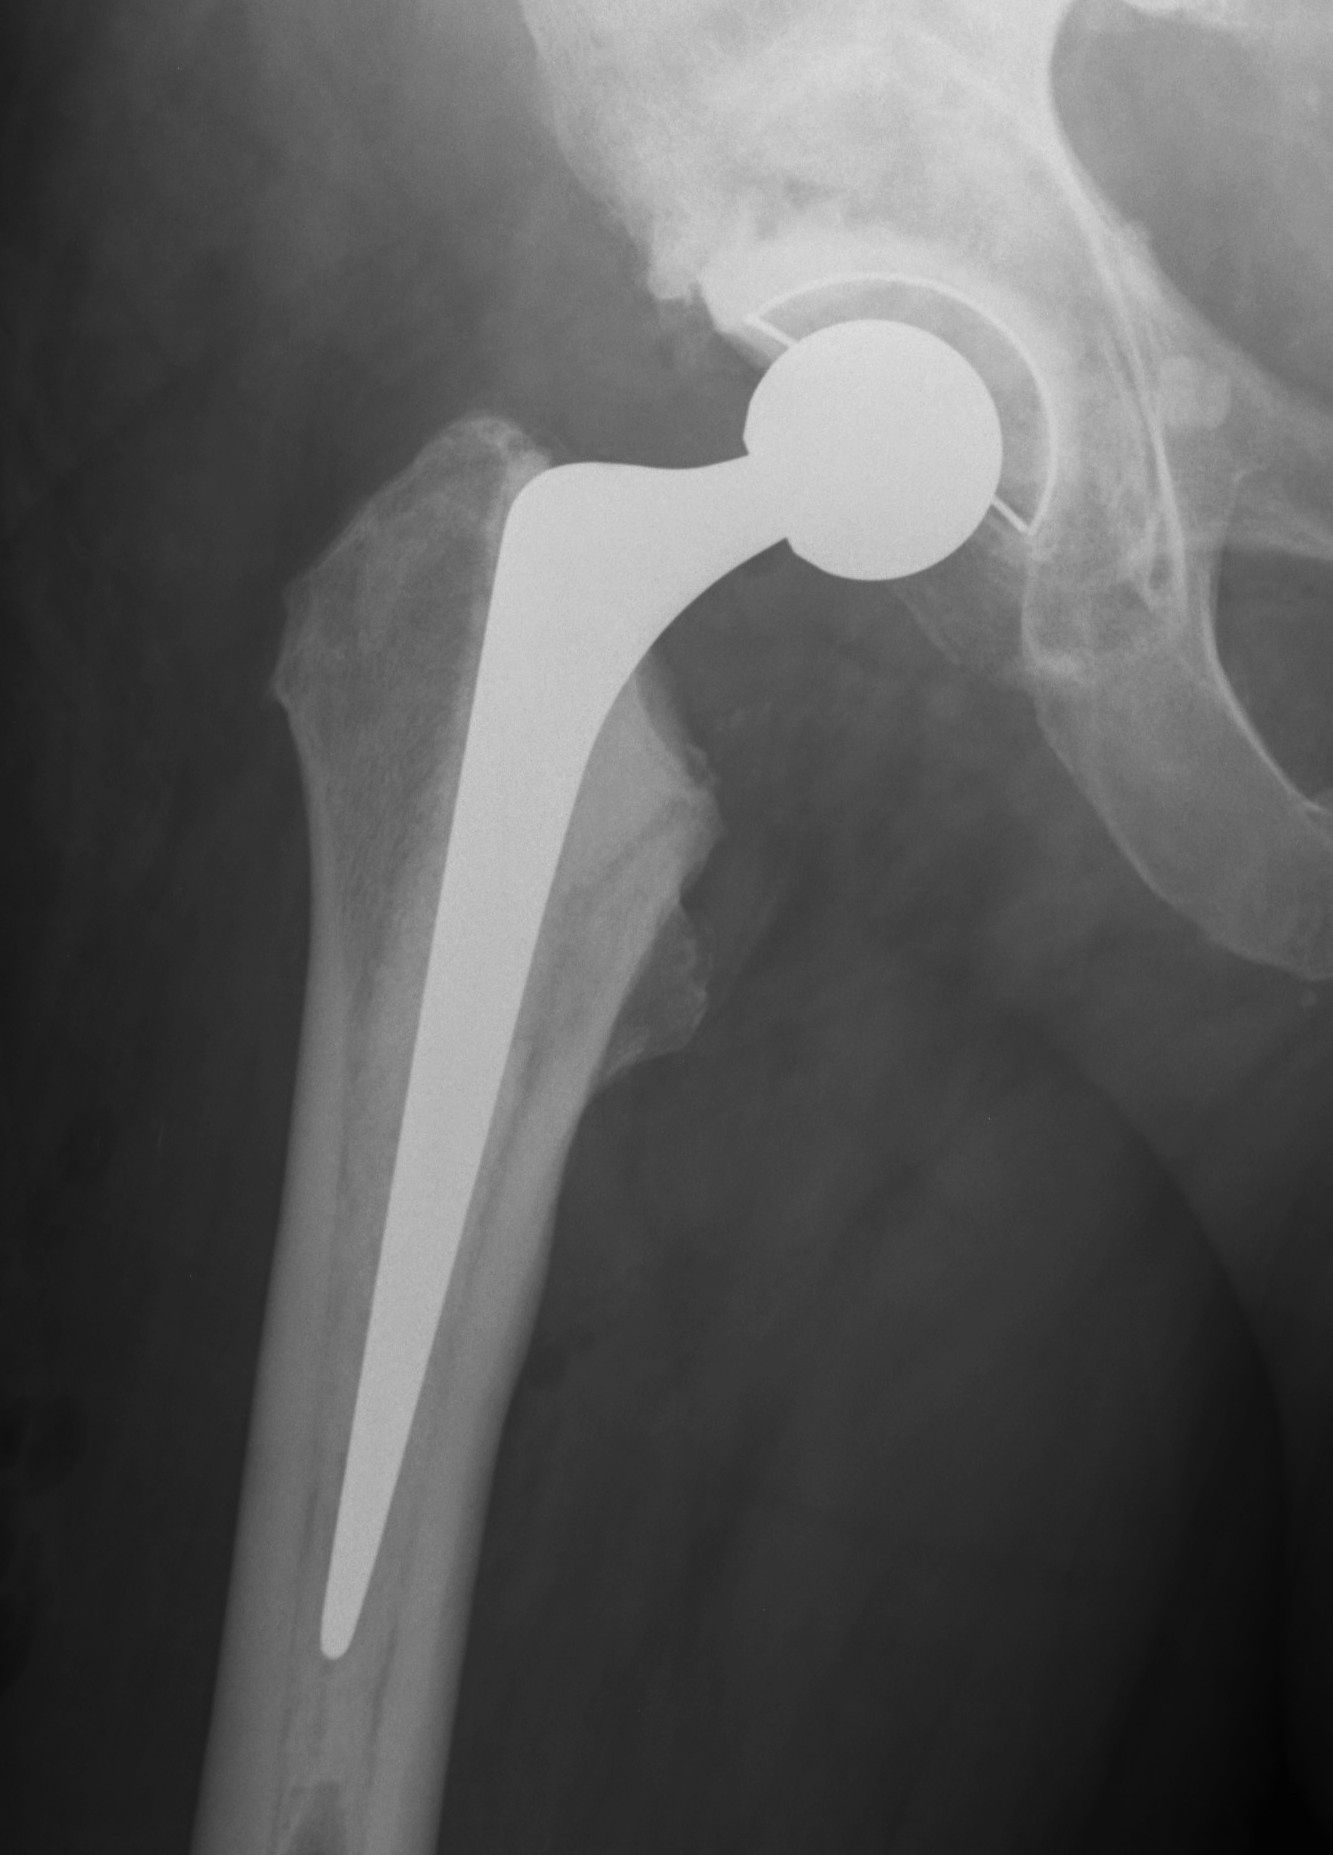

B. Uncemented

Can be very difficult to remove a well fixed stem

- i.e. if removing for infection

Consider component design

- proximally coated

- extensively coated

Breakdown osseointegration

- flexible osteotomes

- sagittal saw

- very difficult

- can perform ETO about stem

Extraction devices

- company specific

- hook under neck